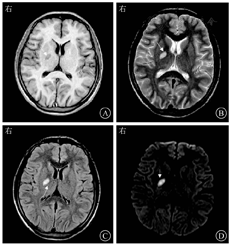

患者男,26岁。因"发热、头痛1个月"于2019年5月6日入南京中医药大学附属南京医院。患者1个月前在无明显诱因下出现全身乏力,伴发热,体温为38.0 ℃左右,无其他伴随症状,当地医院予以输液治疗(具体不详)后体温恢复正常,但出现头痛、恶心,无呕吐,后头痛呈持续性加重,休息后无好转。1 d前患者再次出现发热,体温为38.5 ℃,伴有畏寒、头痛,考虑"中枢神经系统感染",因其HIV抗体阳性,故转入南京中医药大学附属南京医院。患者1年前曾有梅毒病史,自诉于当地医院接受肌内注射苄星青霉素治疗3次后未再复查。患者于2016年确诊HIV-1抗体阳性,并启动拉米夫定+替诺福韦+奈韦拉平抗病毒治疗,1年前自行停止抗病毒治疗,CD4+T淋巴细胞计数和病毒载量均不详。既往有双性无保护冶游史。体格检查:体温为38.5 ℃,脉搏为70次/min,呼吸为20次/min,血压为120/80 mmHg(1 mmHg=0.133 kPa)。神清,精神萎,消瘦貌,言语正常,对答切题,查体合作,全身未见皮疹,皮肤、巩膜未见黄染,颈部淋巴结未触及明显肿大。双侧瞳孔等大、等圆,直径为3 mm,对光反射灵敏,口腔黏膜未见白斑。颈项强直,双肺呼吸音清,未闻及干、湿啰音,心音有力,律齐,未闻及病理性杂音。腹平软,无压痛,肝脾肋下未及,移动性浊音阴性。克尼格征和布鲁津斯基征均为阴性,右侧巴宾斯基征可疑阳性。入院后血液分析、生物化学检查、凝血功能检查均未见明显异常。血清快速血浆反应素试验(rapid plasma regain test,RPR试验)效价为1∶512,梅毒螺旋体明胶凝集试验(treponema pallidum particle assay,TPPA)阳性。单纯疱疹病毒Ⅰ型抗体IgG阳性,单纯疱疹病毒Ⅰ型抗体IgM和Ⅱ型抗体IgG+IgM均阴性;CMV DNA<500拷贝/mL。血MTB抗体、T-SPOT.TB、血隐球菌荚膜抗原、血GeneXpert MTB/RIF、血培养和血分枝杆菌培养均为阴性。CD4+T淋巴细胞计数为57/μL。头颅CT+胸部CT平扫检查未见明显异常;颅脑MRI检查示右侧基底节区有异常信号,感染可能(图1)。行腰椎穿刺术送检脑脊液显示:脑脊液压力为100 mmH2O(1 mmH2O=0.009 8 kPa),脑脊液常规检查显示无色、清晰;潘氏球蛋白试验阴性;有核细胞计数为116×106/L,多核细胞占35%,单核细胞占65%;脑脊液CMV DNA<500拷贝/mL;脑脊液墨汁染色、脑脊液结核分枝杆菌涂片、脑脊液隐球菌荚膜抗原、脑脊液GeneXpert MTB/RIF和脑脊液培养均为阴性;脑脊液梅毒抗体RPR试验阳性(效价为1∶2),TPPA阳性;宏基因组学第二代测序(以下简称二代测序)检测出密螺旋体序列52条,人类疱疹病毒5型(即CMV)序列14条。诊断为神经梅毒,予青霉素钠(每次320万U,每4 h 1次,静脉滴注)进行驱梅治疗,予甘露醇(25 g/次,每8 h 1次,静脉滴注)进行脱水降颅压治疗,予拉米夫定(0.3 g,1次/d)、替诺福韦(0.3 g,1次/d)和洛匹那韦/利托那韦(每次400/100 mg,2次/d)进行抗反转录病毒治疗,患者发热、头痛症状逐渐消退。采用青霉素治疗10 d后,患者再次出现发热,并出现皮疹伴瘙痒,怀疑青霉素过敏反应,改用头孢曲松(每次1.0 g,每12 h 1次,静脉滴注)进行驱梅治疗。完成14 d驱梅治疗疗程后,患者症状逐渐缓解,予以办理出院,随后失访。